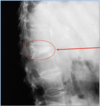

What does this image show? Possible cause?

"Wedge fracture"/ vertebral collapse Can be caused by osteoporotic weakening